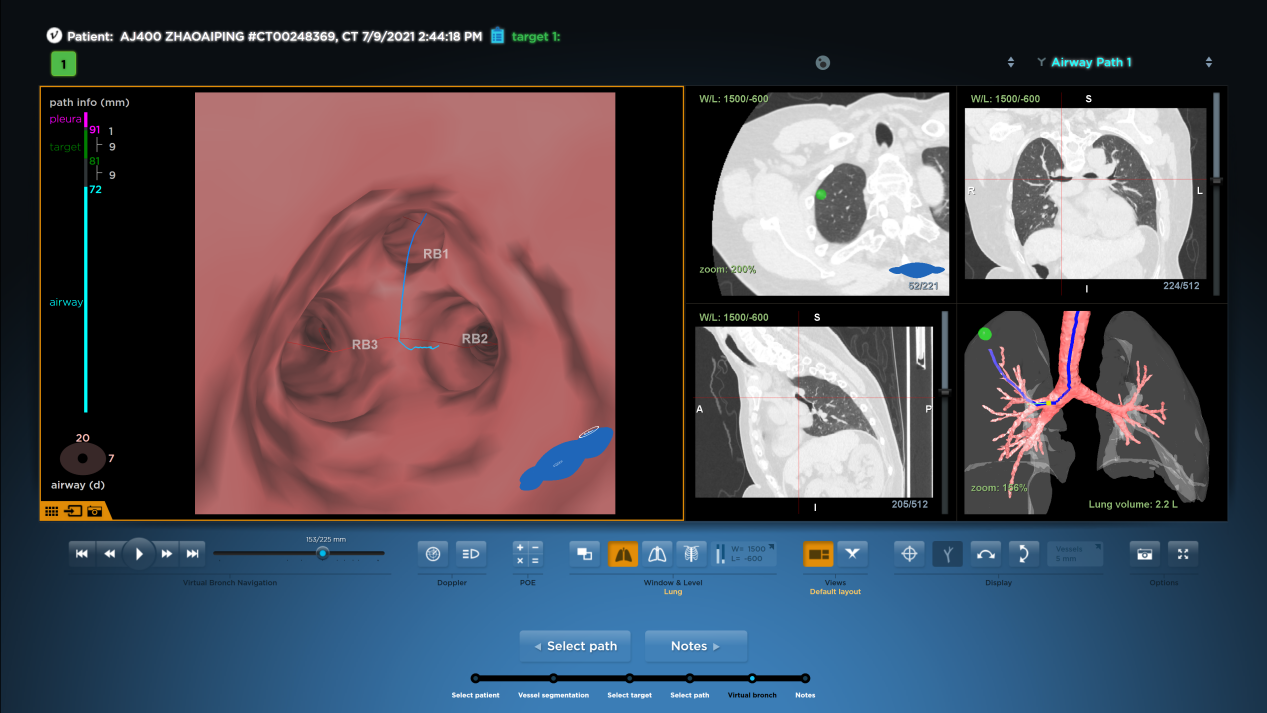

该病灶于右肺上叶尖段可见一磨玻璃结节,结节较小,且位置极高,常规器械滑行或手指触摸定位结节难度较大,为达到精准定位、精准治疗,且有效缩短患者手术时间目的。朱坤寿主任医师及林绍峰副主任医师术前充分讨论,利用Lungpro增强现实支气管导航术前三维重建支气管树,分析病灶与气道位置关系,拟定染色标记胸膜区域。

三维支气管树重建

手术中,麻醉科诱导麻醉后,手术团队采用外径4.0mm的支气管镜,根据支气管导航提供的路径抵达既定位置(RB1亚亚支,约第6级气道),往前推送打药管至病灶附近胸膜处,于此处打入0.2ml美兰染色液,随后缓慢推入空气让染色液逐渐渗透至病灶附近胸膜区域。

导航路径